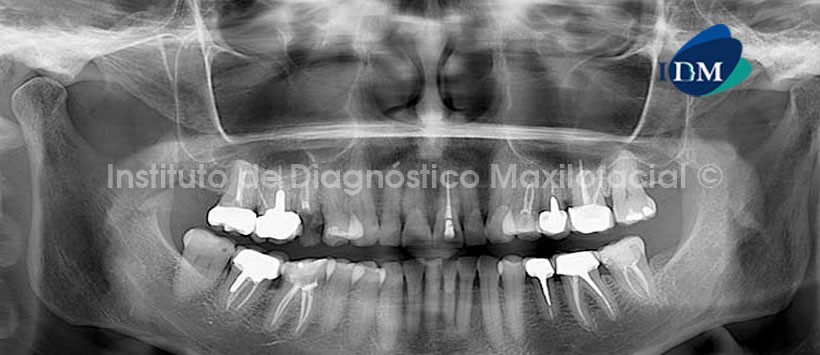

En la radiografía panorámica se observa material de obturación de conductos en múltiples piezas del maxilar superior e inferior en aparente buen estado y la pieza 1.5 presenta lesión cariosa coronaria amplia. No se observan otros cambios significativos en la región a evaluar. (Fig. 1)